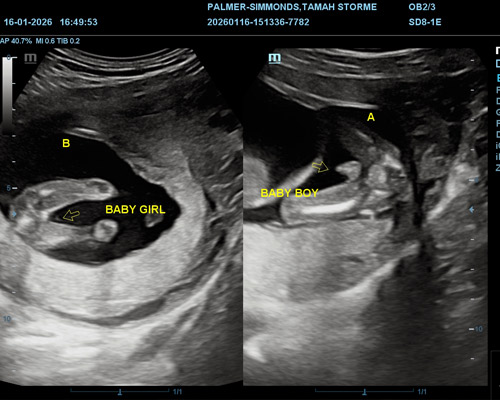

Gender identification for twins is usually possible from around 15 weeks onwards. At this stage, both babies are developed enough for the sonographer to determine their genders, depending on their positions.

- Would like to find out the gender of each baby

Yes, twins can either be the same gender or different, depending on the type of twin pregnancy.